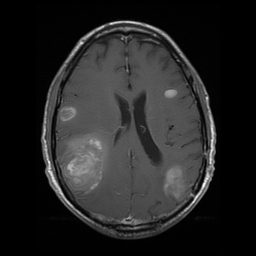

Most often, meningiomas are found incidentally on MRIs leading from a patient visit that was unrelated to the meningioma itself. Because meningiomas arise separately from the brain itself, they usually display a very sharp border between the brain and tumor both on MRI imaging and on microscopic appearance. The microscopic appearance of the tumor determines its grade, a measure of how cancerous the tumor is. The majority of meningiomas are grade I, benign tumors, but occasionally can be grade II (atypical) or grade III (malignant), which are more cancerous.